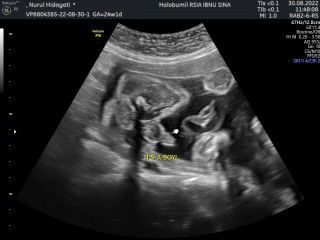

baby boy USG 6 bulan

USG 6 bulan berat 700 gram ,alhmdulillah baby boy